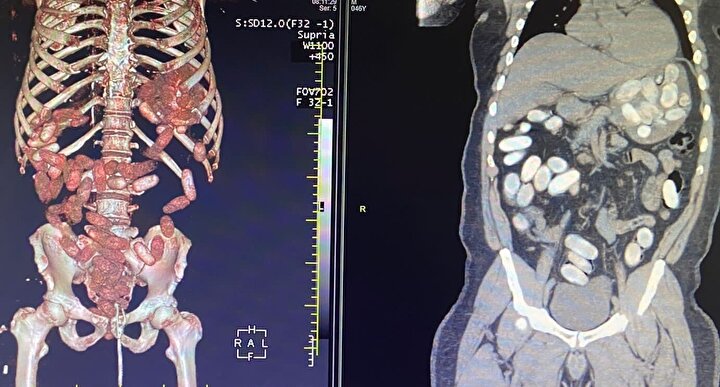

Gümrük Muhafaza ekiplerince savcılık talimatı doğrultusunda detaylı bilgisayar tomografi çekilmesi için sağlık kuruluşuna götürülen 6 yolcunun yapılan tarama ve muayenelerinde toplam ağırlığı 10 kilo 420 gram kokain tespit edildi.

İkinci operasyonda, başka bir yolcunun da "yutucu kurye" olduğu bilgisine ulaşan ekipler, şüpheli kişiyi takibe aldı. Bahse konu yolcuda, yutucu tespit cihazı ve akabinde sağlık kuruluşunda yapılan muayene sonucunda 48 kapsül ve toplam ağırlığı 760 gram kokain ele geçirildi.